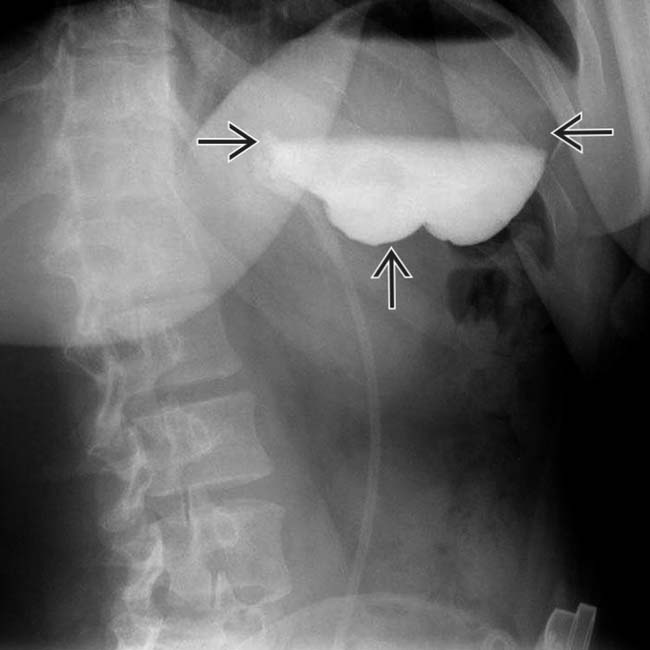

Slipped lap band O sign Image Gastric Band Position Radiology The purpose of this article is to describe a sign on radiography for gastric band slippage, a complication of adjustable gastric banding. This article reviews the most commonly performed bariatric procedures, the normal imaging findings on fluoroscopic upper gi and computed tomography (ct) studies, and the role of imaging studies in detecting complications associated with these procedures. Lagb is a. Gastric Band Position Radiology.

Slippage of gastric band in a 54yearold woman. Abdominal plain Gastric Band Position Radiology Lagb is a restrictive form of bariatric surgery that reduces proximal stomach capacity, thus inducing early satiety and decreased calorie intake. Must be measured with the gastric band in profile. The adjustable soft silicone band, a tube connecting the band to the final part, and the access port (fig 1). Fluoroscopy is a versatile tool in assessing for potential gastric. Gastric Band Position Radiology.

Fig. Fig. 4 Normal barium swallow. Well positioned band with an angle Gastric Band Position Radiology A gastric band is a popular form of bariatric surgery and is a surgically placed device, used to assist in weight loss and is adjustable. 3,7 most lagb consist of three main parts: The adjustable soft silicone band, a tube connecting the band to the final part, and the access port (fig 1). Phi angle is useful to assess position. Gastric Band Position Radiology.